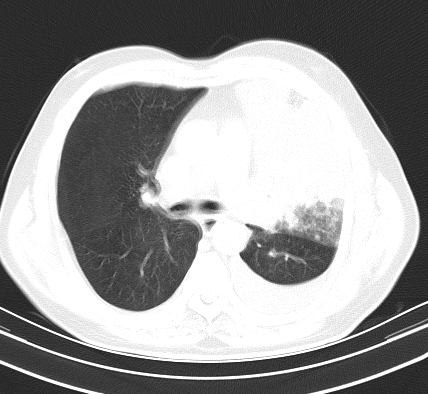

以下是引用老爱克斯新网客在2008-7-31 6:30:00的发言:[br]左肺上叶大片状病灶,左肺上叶支气管狭窄呈鼠尾状,左肺门增大,纵隔内见肿大淋巴结,左侧胸腔积液,余肺清晰。左肺中心型肺癌淋巴结转移,

以下是引用zjb在2008-7-31 6:32:00的发言:[br]左侧中心性肺癌 阻塞性肺炎 肺不张 胸腔积液 建议气管镜

以下是引用zjzjr在2008-7-31 8:45:00的发言:[br]考虑左侧中心性肺癌伴阻塞性肺炎,左肺上叶肺不张,纵隔淋巴结转移;左侧胸腔积液。建议行纤支镜检查。

以下是引用sdzyy在2008-7-31 8:47:00的发言:[br]病灶较治疗前有所进展,胸水增多, 左侧中心性肺癌 并 阻塞性肺炎 肺不张 胸腔积液 可能性大; 建议气管镜检查。 [br] [br]